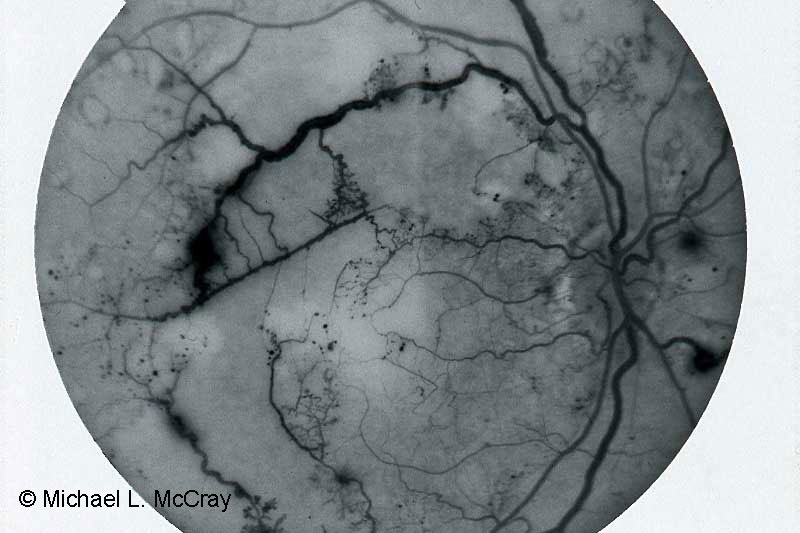

I have primarily earned my living as an ophthalmic photographer. However, I have worked as a photojournalist for daily & weekly newspapers and freelanced covering conflicts in Afghanistan and Central America in the 80’s. I focused on the social and medical issue in conflicts and was able to generate support from the medical community here and overseas.

My knowledge of pathology landed me a position as Community Outreach Coordinator for Cleveland Eye Clinic. I led a team which screened over 45,000 people in NE Ohio communities for vision problems which received national recognition. In the evenings I provided vision screenings for Health Care for the Homeless’ outreach in Cleveland for a number of years.

It was during this time that I started Iris Imaging to provide services to the eye care community of NE Ohio.